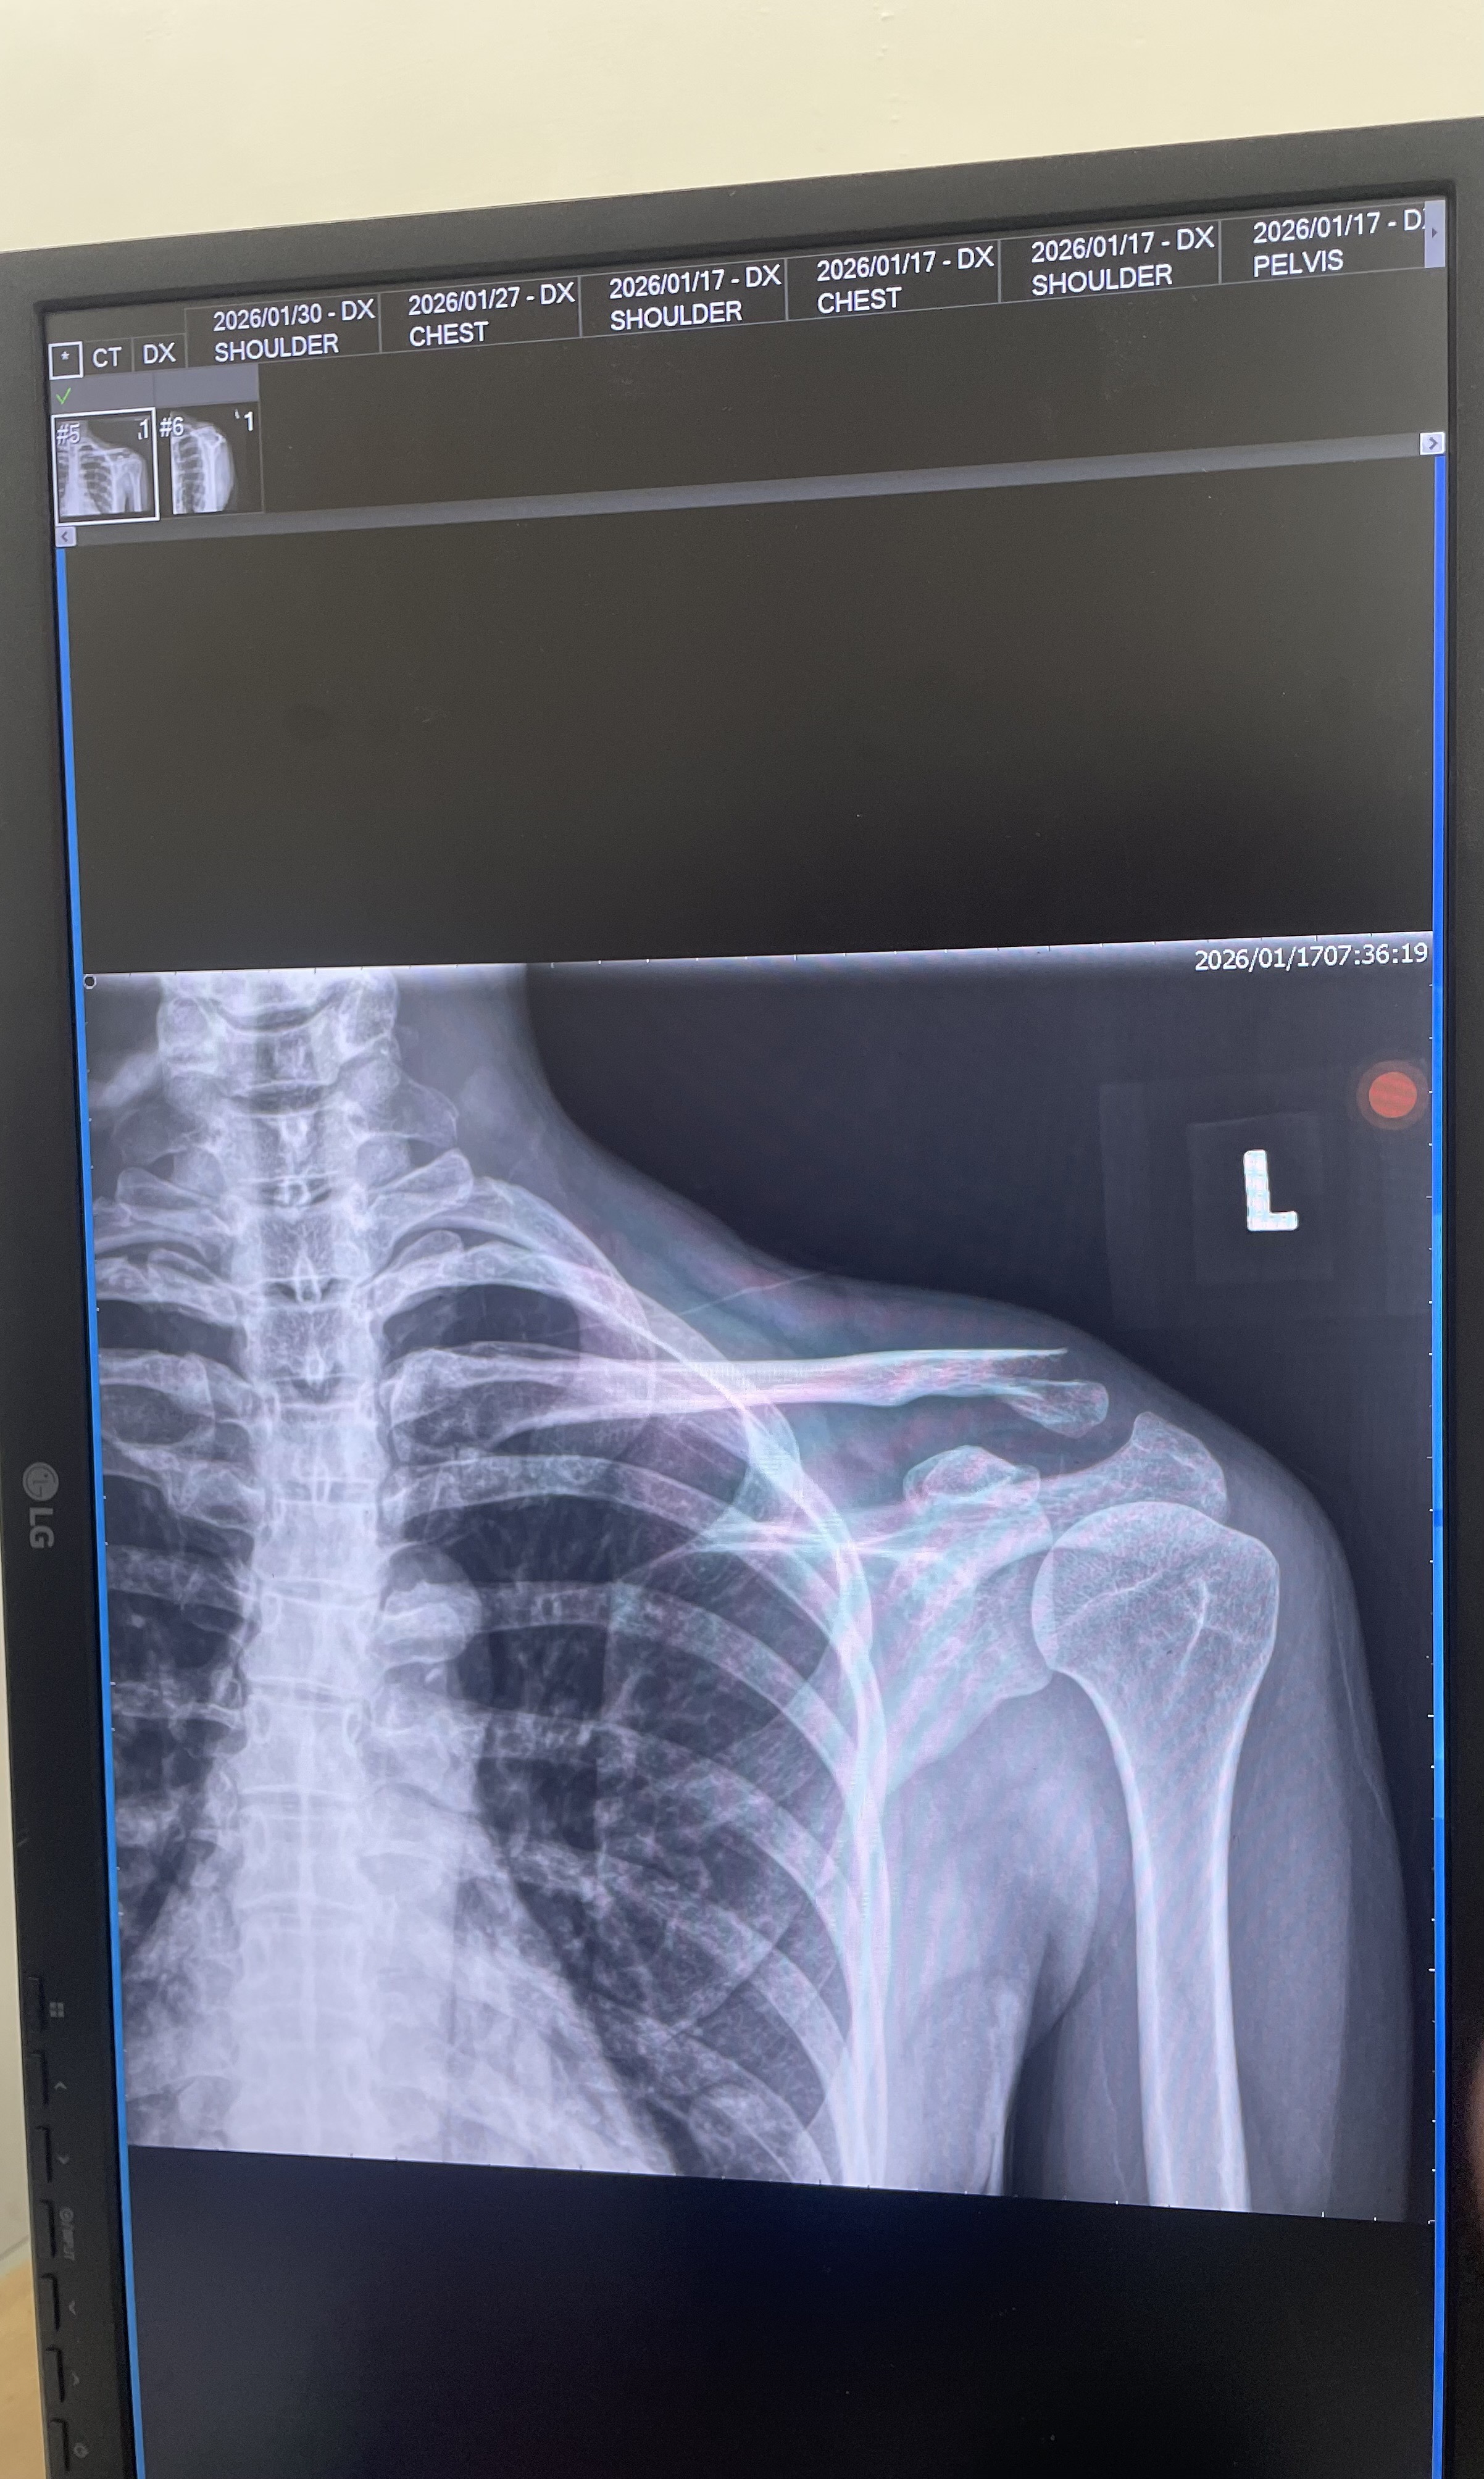

民國 115 年 1 月 17 日,原告楊雅雯(Doris)參加東三塔自行車活動時,被告翁思浩從後方違規切入車道,後輪撞上原告前輪,導致原告摔車,造成左側鎖骨骨折,緊急手術植入鈦金屬骨板,醫囑恢復需一年以上。

左側遠端鎖骨位移性骨折,手術植入鈦金屬骨板,恢復需一年以上

其中特殊材料費(鈦骨板)自費高達 $124,668。另依診斷證明書醫囑「需專人照護約兩個月」,看護費以每日 $2,200 計算共 $132,000。

東三塔自行車挑戰活動,台2線 32.3K。原告左側鎖骨骨折,緊急手術植入鈦骨板。

X光、手術傷口、擦挫傷